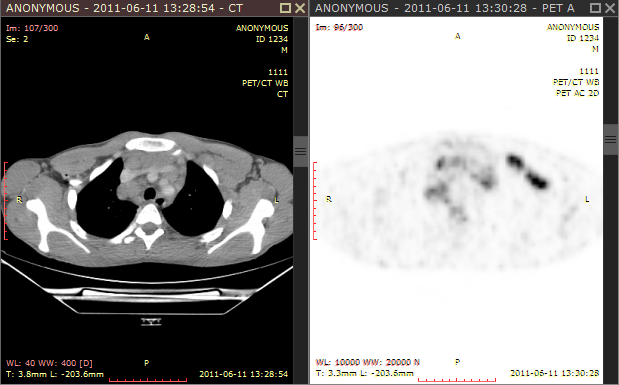

1) Use the screen splitting tool to open CT and PET series in two panels.

2) Activate the panel with CT series by clicking the image it contains or its title bar.

3) Click the Fusion button on the toolbar or use the Ctrl + Alt + F shortcut.

The default color scale used for rendering a fused image is set to "Hot iron". It can be changed by clicking a bar with a color scale to the left side of the image.

The range of values represented on a color scale is adjusted by using the windowing tool in the panel with the series used as overlay (PET).